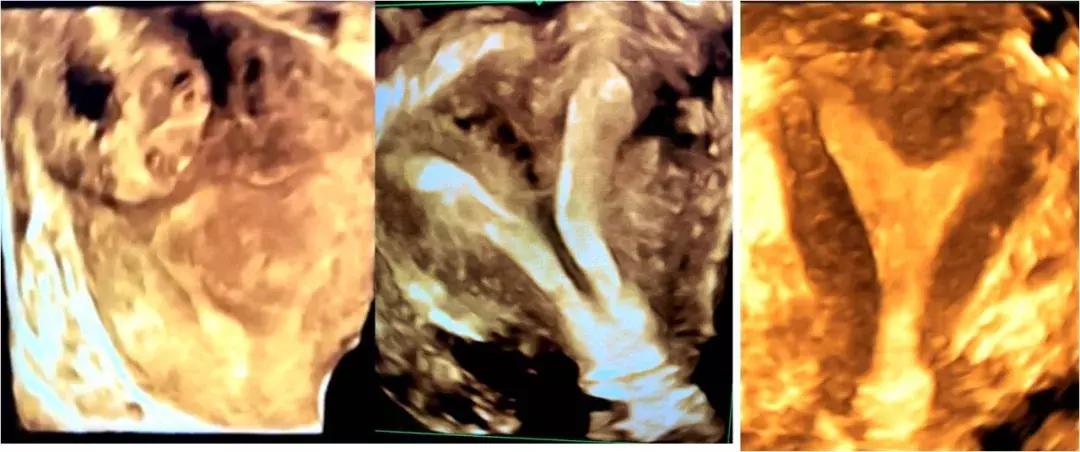

腔内四维超声(4D-TVS)是在腔内二维超声基础上,利用计算机在处理功能发展起来的新型超声诊断技术,可以提供更多的诊断信息,具有常规的经阴道超声无法比拟的优势,立体直观,功能强大,像素高清,可谓360度全方位无死角。超声科团队在郑瑜主任的带领下,在我院妇科专家的大力支持下,不断积累与探索,完成技术攻关与技术培训,已为多名患者提供该项新技术检测服务,大大弥补了单纯二维腔内超声的不足。

随着辅助生殖技术的蓬勃发展,现有的二维腔内超声远远不能满足不孕症超声越来越高的精准化诊断要求,腔内4D-TVS通过海量数据运算形成四维数据库,能获得高清冠状切面图像及可360度旋转的子宫内膜三维立体图,非常有利于进行不孕症子宫内素分析,对先天性子宫畸形(完全或不完全纵膈子宫、弓状子宫、双角子宫、单角子宫、残角子宫等)、宫腔粘连、内膜息肉、粘膜下肌瘤的鉴别诊断,还能清晰的观察到节育器的形态、位置,对判断节育器发生移位、旋转、断裂、肌层嵌顿等有一定的价值,大大提高了超声在妇科疾病诊断中的准确率,为临床医生提供更准确的诊断信息,同时填补了我市在此项技术的空白,我科赵洁主治医师连续两次在省级医学年会上代表我科做了《实时三维超声诊断宫腔粘连及分级》的专题汇报,并获陕西省超声学会优秀论文二等奖。

近日,一患者早孕期子宫异常出血,外院超声诊断宫角妊娠,我院常规妇科超声检查发现患者子宫宫底偏左侧混合性包块,但似与宫腔不相连,与患者沟通后,行经阴道三维超声检查,得到了清晰的图像,明确的看到孕囊与宫腔间可见窄带样间质线征及混合包块的血供,诊断为间质部妊娠。妇科医生根据三维超声检查结果及时给予患者手术治疗,避免了异位妊娠破裂大出血的风险。一例多年连续早孕期流产的38岁女士,多次做常规超声都没有发现明确问题,妇科医生建议她来行4D-GYN超声,经过仔细检查比对,发现宫角处及宫体有内膜粘连,同时宫底内凸呈浅纵隔子宫,后经宫腔镜诊断证实并给予相关治疗。